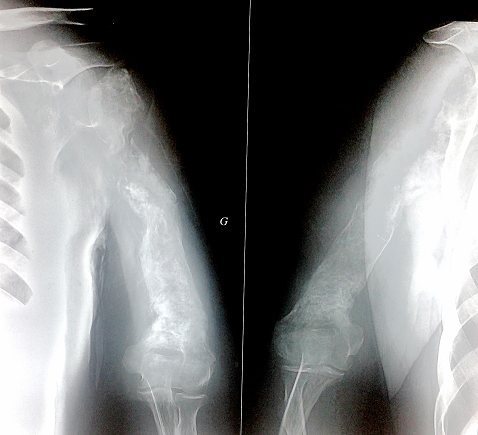

Primary bone lymphoma is a distinct disease. It represents only 3% of all malignant bone tumours and less than 1% of non-Hodgkin's lymphoma. It is essential to differentiate it from other tumours because of its good prognosis. We report a case of 45 years old male who presented one year ago with a painful left arm. His symptoms started after minimal trauma. The pain persisted for 6 months and became severe. It was managed by traditional medicine a practitioners who diagnosed it as a shoulder's sprain and did several massages sessions. The patient had worsening of his pain. On physical examination, shoulder movements were painful. Left arm was entirely swell. Superficial lymph nodes were not enlarged. The X-ray radiograph of the left upper extremity showed a fracture of the proximal humerus and large condensation lesion of the all humerus. Patient was posted for an open biopsy which revealed a primary diffuse large B cell lymphoma. Flow cytometric immunophenotyping showed positivity for CD10, CD20 and BCL6 and negativity for CD5, MUM1 and BCL2. Bone marrow and cerebrospinal examinations were normal. Contrast enhanced computed tomography of chest and abdomen failed to show evidence of any lymphomatous deposits. The patient was treated with chemotherapy including cyclophosphamide, doxorubicin, vincristine, and prednisolone with a good clinical response. He has been lost to follow up after five cycles of chemotherapy because of financial problem. The diagnostic study should begin with simple X-ray but adequate biopsies for histologic examination remain the standard in diagnosis.